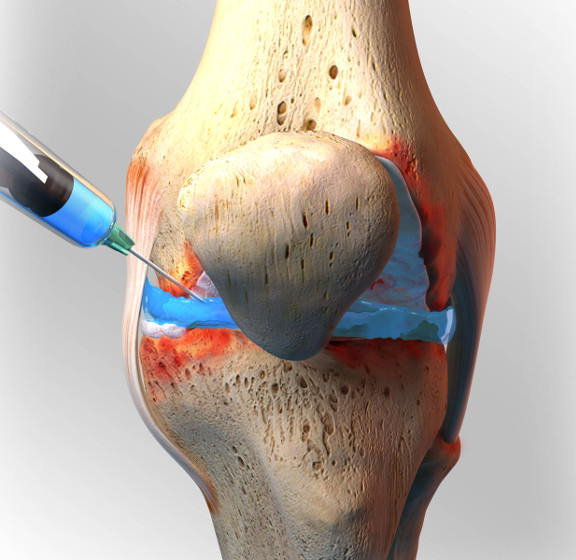

Bursitis

BURSITIS Y SINOVITIS